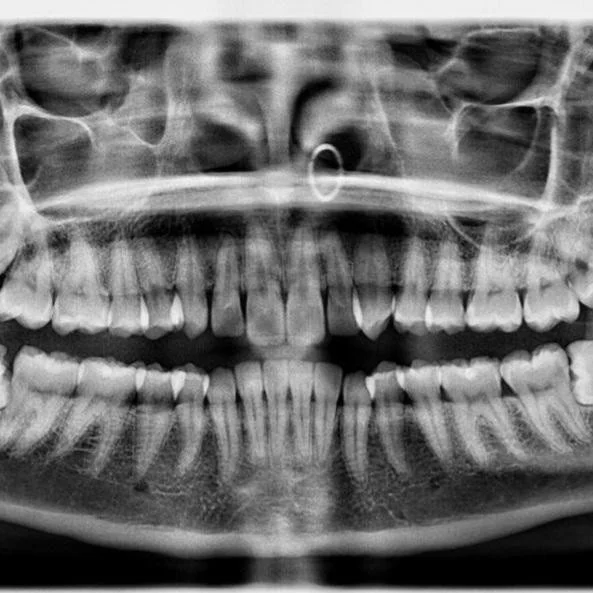

Просто пирсинг в носу

Сережки на снимке